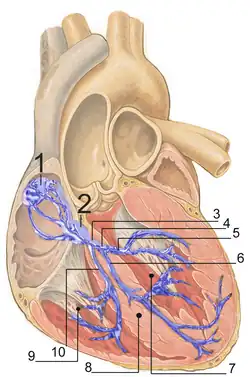

Sistema de condução elétrica

O coração possui um sistema excitatório que lhe permite gerar impulsos elétricos rítmicos e um sistema de condução que lhe permite conduzir rapidamente esses impulsos. Os impulsos provocam a contração rítmica das células cardíacas, provocando o batimento cardíaco. Esses impulsos elétricos são denominados potenciais de ação cardíacos e são produzidos por alterações químicas nas células marca-passo do nódulo sinusal.[15]

O ritmo cardíaco normal em repouso do coração é denominado ritmo sinusal. Este ritmo é produzido pelo nódulo sinusal, um grupo de células marca-passo situadas na parede superior da aurícula direita, perto da união com a veia cava superior.[28] Estas células produzem um potencial de ação a partir do movimento de eletrólitos específicos para dentro e para fora das células. Esse potencial de ação cardíaco, ou impulso elétrico, propaga-se depois para as células nas proximidades.[29]

O sinal elétrico gerado pelo nódulo sinoatrial percorre a aurícula direita de forma radial e chega à aurícula esquerda através do feixe de Bachmann, fazendo com que ambas as aurículas se contraiam ao mesmo tempo.[31][32][33] Em seguida, o sinal passa para o nódulo atrioventricular, situado na parte inferior do septo atrioventricular. O septo faz parte do esqueleto cardíaco, o qual é constituído por tecido colagenoso que o sinal elétrico não consegue atravessar, o que força o sinal a passar apenas pelo nódulo auriculoventricular.[7] O sinal percorre então o feixe de His e os seus dois ramos através dos ventrículos do coração. Nos ventrículos, o sinal é transportado por um tecido especializado denominado fibras de Purkinje, que por sua vez transmitem o sinal elétrico ao músculo cardíaco.[34]